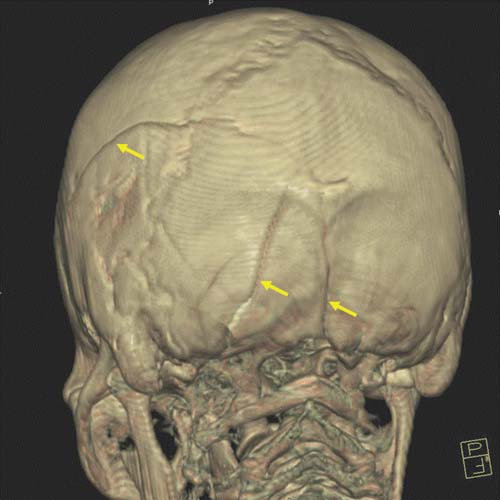

Whereas in cases of sharp trauma the type of inflicting instrument may be discerned in most cases, this is not true for all contusions and lacerations of the scalp. For instance, it is obviously of utmost importance to distinguish between scalp contusions, due either to a fall or to a blow with an instrument. The fracture pattern of the skull and typical cerebral lesions can solve this problem with a large degree of certainty. If the head strikes a broad, flat surface, such as the ground, the skull is flattened at the point of impact. Due to this resulting inward bending, distant areas of the skull are bent outward. Fractures do not begin at the point of impact but at the point of outbending at the external surface [10,11]. For instance, a fall with a low-energy impact to the occipital skull will therefore classically lead to linear fractures (Figure D3.2.10). If the impact of the large, flat surface is great enough, complete or incomplete circular fractures may arise around the impact point at the edge of inward and outward bending. With an even greater amount of energy, the severe inbending at the point of impact leads to stellate fractures arising from the impact center. A combination of circular and stellate fracture lines creates a distinct spider web-like fracture system. Later fracture lines will not cross preexisting fracture lines, as the necessary tension is lacking in previously fractured areas. This phenomenon, also known as the "Puppe-rule" can help assess the timing of skull injuries when more than one impact point is seen.

If the impact occurs with high energy and a small surface area, i.e., in blows with hammers, the result is a small, depressed skull fracture (Figure D3.2.11 and Figure D3.2.12). Here, the brain is generally only affected in the immediate vicinity of the impact. A blow to the head (i.e., the occiput) will therefore mainly result in a cerebral injury to the occipital brain regions. Several blows to the head can obscure the small, depressed fracture due to the severe destruction of the concerned skull region. By contrast, a fall from great height or from an upright position onto the ground will lead to a completely different fracture pattern and cerebral injury (Figure D3.2.13). Here, linear or, if the energy involved is great enough, circular fractures are commonly encountered. Simple linear fractures are, however, also seen in (lowenergy) blows to the head. In these cases, the plain radiograph of the skull does not suffice to distinguish between a blow and a fall. Here, postmortem MSCT imaging can deliver quick and reliable results. By enabling the visualization of the brain, coup-contrecoup lesions can be detected. This constellation of impact-near and impact-far injuries is often seen in falls. They are an absolute rarity in cases of homicidal blows to the head. Thus, by visualization of the brain, the pathologist may be able to discern between a blow and a fall even if the external wound morphology may be obliterated or hidden (e.g., due to secondary animal involvement such as ants). The cerebral injuries inflicted by blows and falls are discussed in detail in Chapter D3.3.

Indirect blunt traumas of the head encompass changes of velocity. The head is relatively heavy. The resulting inertia can lead to various lesions, typically of the skull base. These fractures of the skull base can be of great reconstructive value. If the fractured area is dislocated into the fossa posterior, the lesion must have occurred due to a deceleration of the head toward the spine in a stamp-like manner [12]. Such a constellation is seen in cases from falls from great heights such as suicidal falls onto the feet or in parachute accidents. The opposite is true for a rapid acceleration of the head from the spine. As the skull base is firmly attached to the spine by a multitude of ligaments, traction will result in a tearing of the skull base from the remaining cranium [13]. This rather rare finding is seen in cases such as motorcycle accidents.

The relative weight of the head, together with the additional weight of the helmet, can tear the head from the neck in the case of a frontal collision. Torsion of the calvaria from the skull base (Figure D3.2.14 and Figure D3.2.15) has also been described as a mechanism for skull base ring fractures [14]. Another form of indirect blunt trauma of the head is seen in cases of shaken baby syndrome. This very controversial topic is discussed in Chapter D3.3.